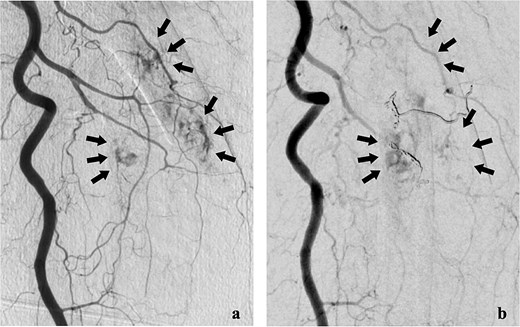

She was transferred to the catheterization laboratory, where coronary and lower extremity angiography revealed 90% stenosis of the left anterior descending artery and tumour blood supply via branches of the deep femoral artery (Figs 2a and 3a).

Lower extremity angiography. (a) Pre-embolization angiography showing tumour blush in the femur. (b) Post-embolization angiography showing tumour devascularization.

After a multidisciplinary team (MDT) review, transcatheter arterial embolization was initially performed for the bone metastasis. The tumour received blood from two deep femoral artery branches, and embolization with gelatin sponges and coils achieved adequate devascularization (Fig. 2b).